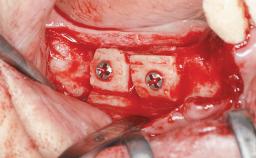

Bone Augmentation Horizontal|Simultaneous|Sinus Floor Elevation|Staged

Augmentation Materials Xenogenous|Membrane